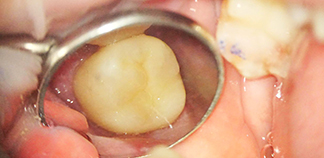

Результаты лечения пациентов

До лечения

Жалобы на длительную непрерывную боль ноющего характера.

Пациенту 45 лет.

Как лечили

Проведено перелечивание корневых каналов. Зафиксирована коронка на зуб.

Лечащие врачи

ЗАВОДОВ Олег Игоревич, ЯСАКОВА Мария Сергеевна